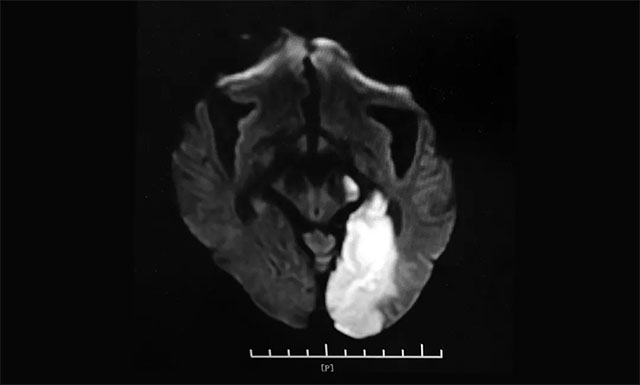

▲ 左侧大脑半球大面积新发脑梗塞

当时患者血压收缩压167mmHg,舒张压97mmHg,GCS评分15分,查ECG示心房颤动,血糖5.4mmol/L,考虑为急性脑梗死。急查头颅CT未见新发出血,行头颅CTP+CTA示左侧大脑半球低灌注,大血管未见明显闭塞,考虑远端分支血管闭塞,遂予以药物保守治疗。